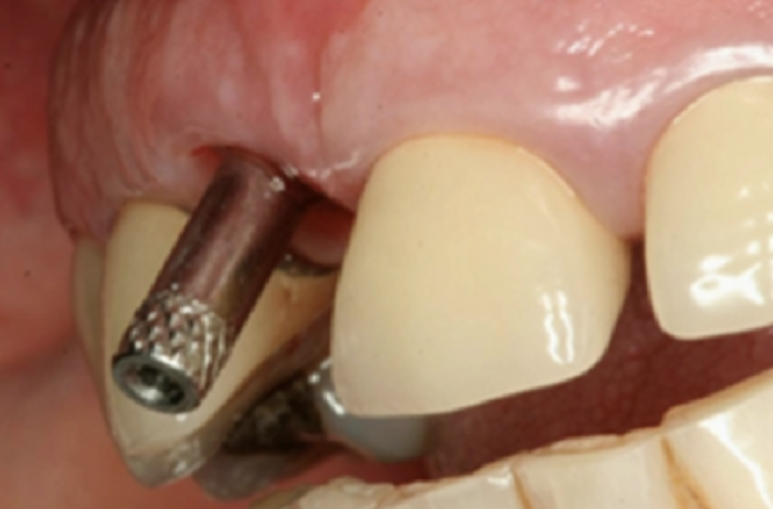

임플란트가 너무 순 측에 위치하여 뿌리 나사 부분이 잇몸 밖으로 노출된 경우

이런 케이스가 가장 안타까운 케이스인데요, 심어진 위치가 너무 잇몸 바깥쪽인 경우 몇 년 지나지 않아 잇몸이 퇴축되어 나사산이 노출되는 경우가 생긴답니다. 물론 정상적으로 심겼으나 임플란트 주위염이 너무 심해져서 생기는 경우도 있고요. 이런 경우 다시 잇몸 이식 및 뼈이식 등을 통해 다시 복원하는 방법도 있지만, 때로는 나사를 제거하고 다시 식립해야 하는 경우도 생기고요. 미국에서 일반 치과의사가 앞니 임플란트를 심었다가 저런 일이 생기는 경우 바로 소송 직행에 자칫 잘못하면 평생 쌓아 올린 치과의사 커리어가 한방에 끝나기 때문에, 앞니 임플란트는 더더욱 전문의에게 맡긴답니다. 500만 원 벌려다가 면허 날아가는 상황이 생길 수 있는 거죠.